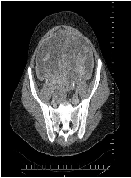

The prevalence of Hjortsjo Crook Sign of Right Posterior Sectional Bile Duct and Bile Duct Anatomy in ERCP of 237 Patients